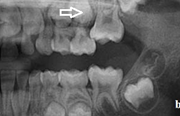

) Röntgenülesvõte. Ülemise esimese jäävmolaari lõikumine on takistatud 2. piimamolaari tõttu

Esimese jäävmolaari ektoopiline lõikumine

Ravijärgne seis. Jäävhammas on täielikult lõikunud.